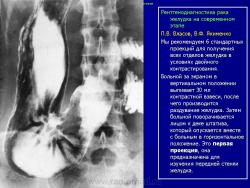

"Лучевая семиотика" рака желудка

Мы предлагаем определенный симптомокомплекс, характеризующий начальные проявления рака желудка, названного нами внутристеночным бластоматозным инфильтратом. Его основные признаки: неровность контура желудка на протяжении 1-3 см и, соответственно, на этом уровне утолщение стенки за счет ее опухолевой инфильтрации.

Сегодня следует говорить о двух основных рентгенологических симптомах рака желудка: неровность его контура в фазу плотного наполнения бариевой взвесью и утолщение стенки желудка, выявляемое с помощью двойного контрастирования. Оба этих симптома имеют весьма многогранную палитру своего отображения: от буквально мизерных признаков неровности контура желудка и очень незначительной (до 3-4 см) по протяженности и степени утолщения стенки при двойном контрастировании.

Характерными лучевыми признаками "малого" рака являются неровность контура желудка на небольшом протяжении (1-3 см), выявляемое при плотном наполнении и соответственно этому участку утолщение стенки при двойном контрастировании. Ригидность стенки желудка, свойственная распространенным формам рака желудка, обычно определяется лишь при размерах опухоли от 3-4 см и более и часто сочетается с изъязвлением.

Двойное контрастирование имеет преимущество главным образом при выявлении "малого" рака тела и верхнего отдела желудка. Однако в ряде случаев оно позволяет детализировать характер изменений и в его дистальном отделе, особенно при наличии опухолевой инфильтрации, приводящей к утолщению стенки, что особенно характерно для эндофитного рака.